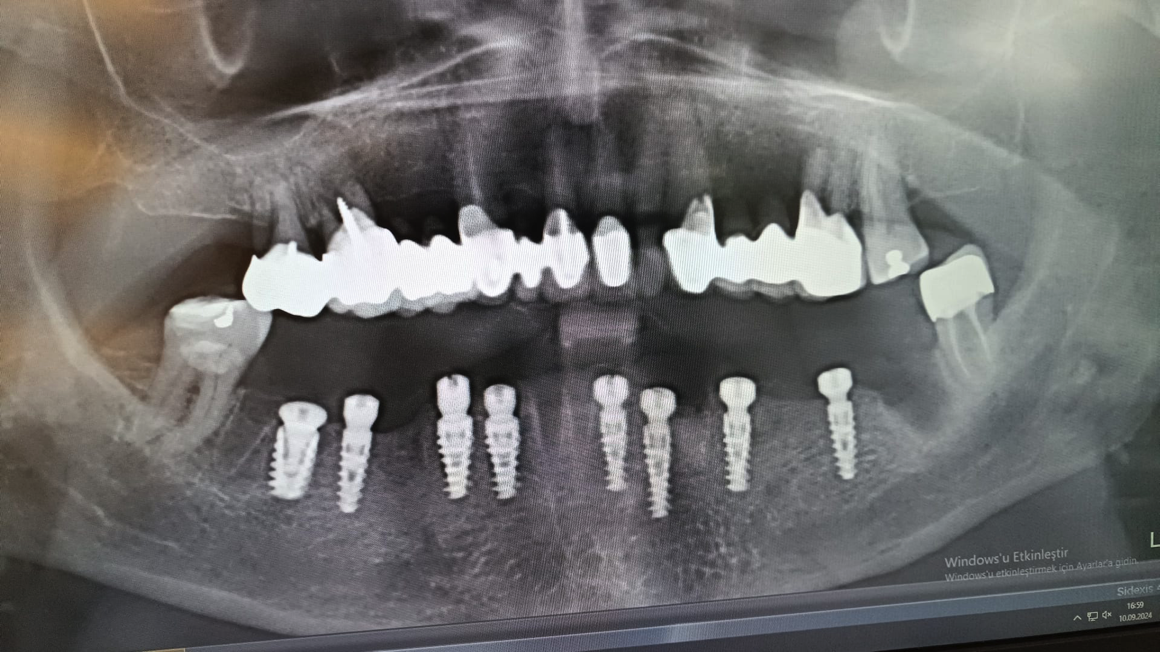

İmplantın boyun (koronal) bölgesindeki özel mikro-yiv yapısı, çiğneme kuvvetlerini kemiğe homojen bir şekilde dağıtır.Krestal kemik emilimini (rezorpsiyon) minimize ederek, implant çevresindeki yumuşak doku estetiğini uzun yıllar korur.

İmplantın boyun bölgesindeki mikro-yiv yapısı, stres dağılımını optimize ederek krestal kemik sağlığını korur. Uzun vadeli estetik başarı ve peri-implantitis riskinde azalma.

İmplant ve protez parçaları arasında sağlanan sızdırmaz (Conical Seal) bağlantı sistemi, parçaların birbirine kusursuz bir şekilde kilitlenmesine olanak tanır. Bu hermetik yapı, mikro sızıntıları ve bakteri infiltrasyonunu tamamen engelleyerek implant çevresindeki yumuşak doku sağlığını garanti altına alır ve mekanik vidaların gevşeme riskini ortadan kaldırır.